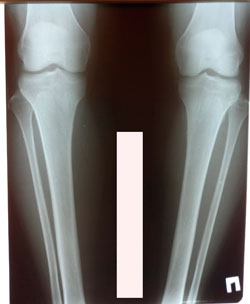

Исходник - 34 года.

Дата операции - 10.02.2021